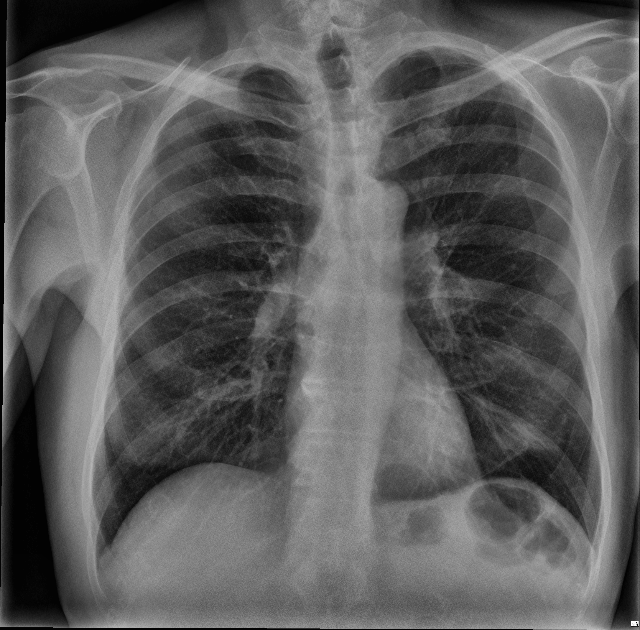

The most common imaging technique used as the first clinical step for chest-related diseases is CXR [26]. Hence, more CXRs could be collected publicly than CT images. A batch of randomly selected samples from the dataset with frontal view, also known as anteroposterior (AP) or posteroanterior (PA), is shown in Fig. 1.

Figure 1: Randomly selected frontal CXR images from different sources